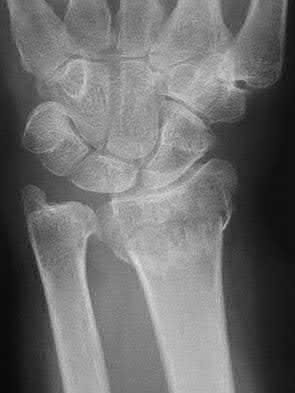

A 51-year-old female presents with an acute inability to extend her thumb, four months after she was treated with cast immobilization for a minimally-displaced distal radius fracture. What is the most appropriate treatment at this time?

A rare complication of non-displaced or minimally displaced fractures of the distal radius treated with a cast is a delayed rupture of the extensor pollicis longus (EPL) tendon. The EPL is the primary extensor of the interphalangeal joint of the thumb and also assists with metacarpophalangeal extension.

Extensor indicis proprius transfer to the EPL is the most widely used and reported treatment for this condition.

Magnussen et al. reviewed results of EIP transfer following ruptures of the EPL, with 19/21 good results. None of the cases had any loss of independent index finger extension although index extensor strength reduced to half of that of the contralateral side.

Hove et al. reported a similar satisfaction rate following treatment of 15 patients. In his series of 4,400 distal radius fractures treated over a 5 year period, the incidence of delayed tendon rupture following distal radius fracture was 0.3 percent.